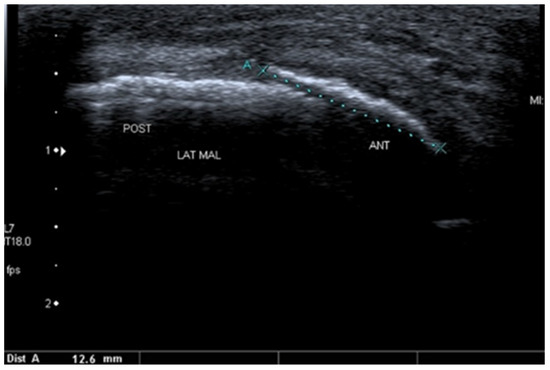

3.2.3. Ligament Injuries

- Szczepaniak, J.; Ciszkowska-Łysoń, B.; Śmigielski, R.; Zdanowicz, U. Value of ultrasonography in assessment of recent injury of anterior talofibular ligament in children. J. Ultrason. 2015, 15, 259–266. [Google Scholar] [CrossRef]